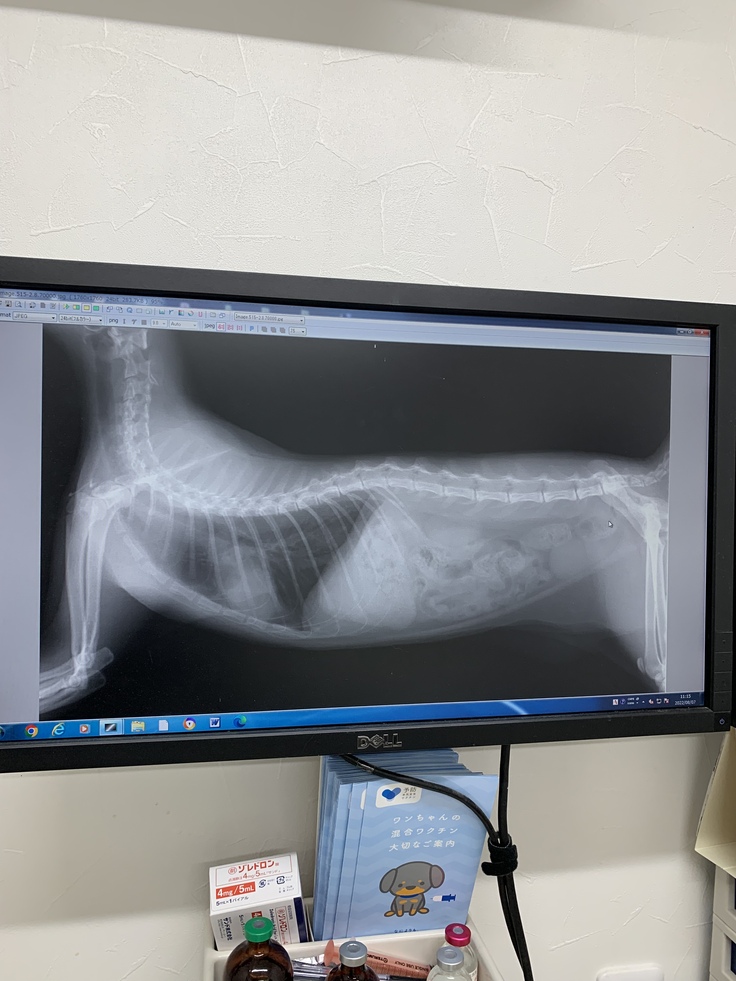

レントゲン改善。

右:再度悪化した際のレントゲン(4回目治療前)

左:オンコビン投与後(5回目治療前)

病気様に記載許可を頂いています。

他の抗がん剤(オンコビン)に再挑戦。